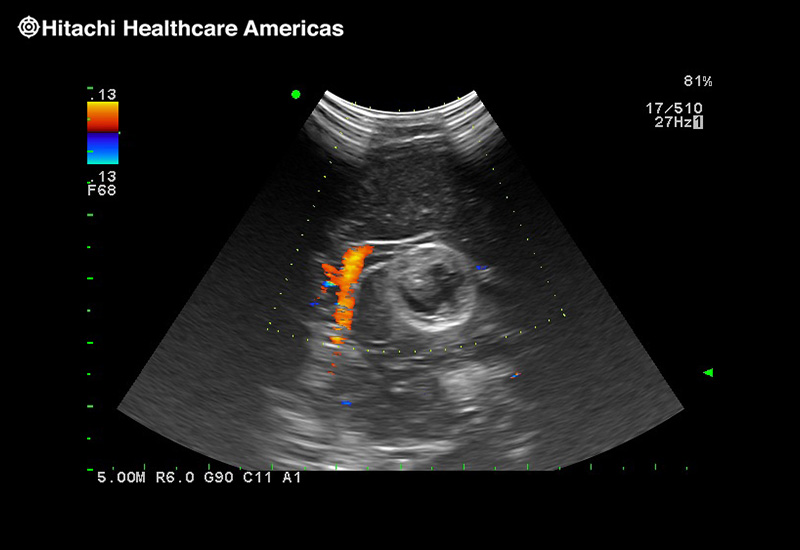

Giving the surgeon complete control

The Fujifilm Healthcare transducer utilizes the full benefits of the Wrist Articulation™ of the robotic instruments to capture real-time ultrasound imaging even at complex angles and difficult-to-reach areas.

The next level in Robotic Ultrasound

Full wrist articulation with optimized functional length.

A critical function of robotic ultrasound guidance is tumor margin identification. Fujifilm's family of robotic probes all have the optimum location of the attaching mechanism that allows for full wrist articulation of the probe. The result is an increased confidence that the tumor margins have been completely identified.

Imaging Clearly Defined

State-of-the-art digital architecture and advanced imaging features to redefine the capabilities of surgical ultrasound.